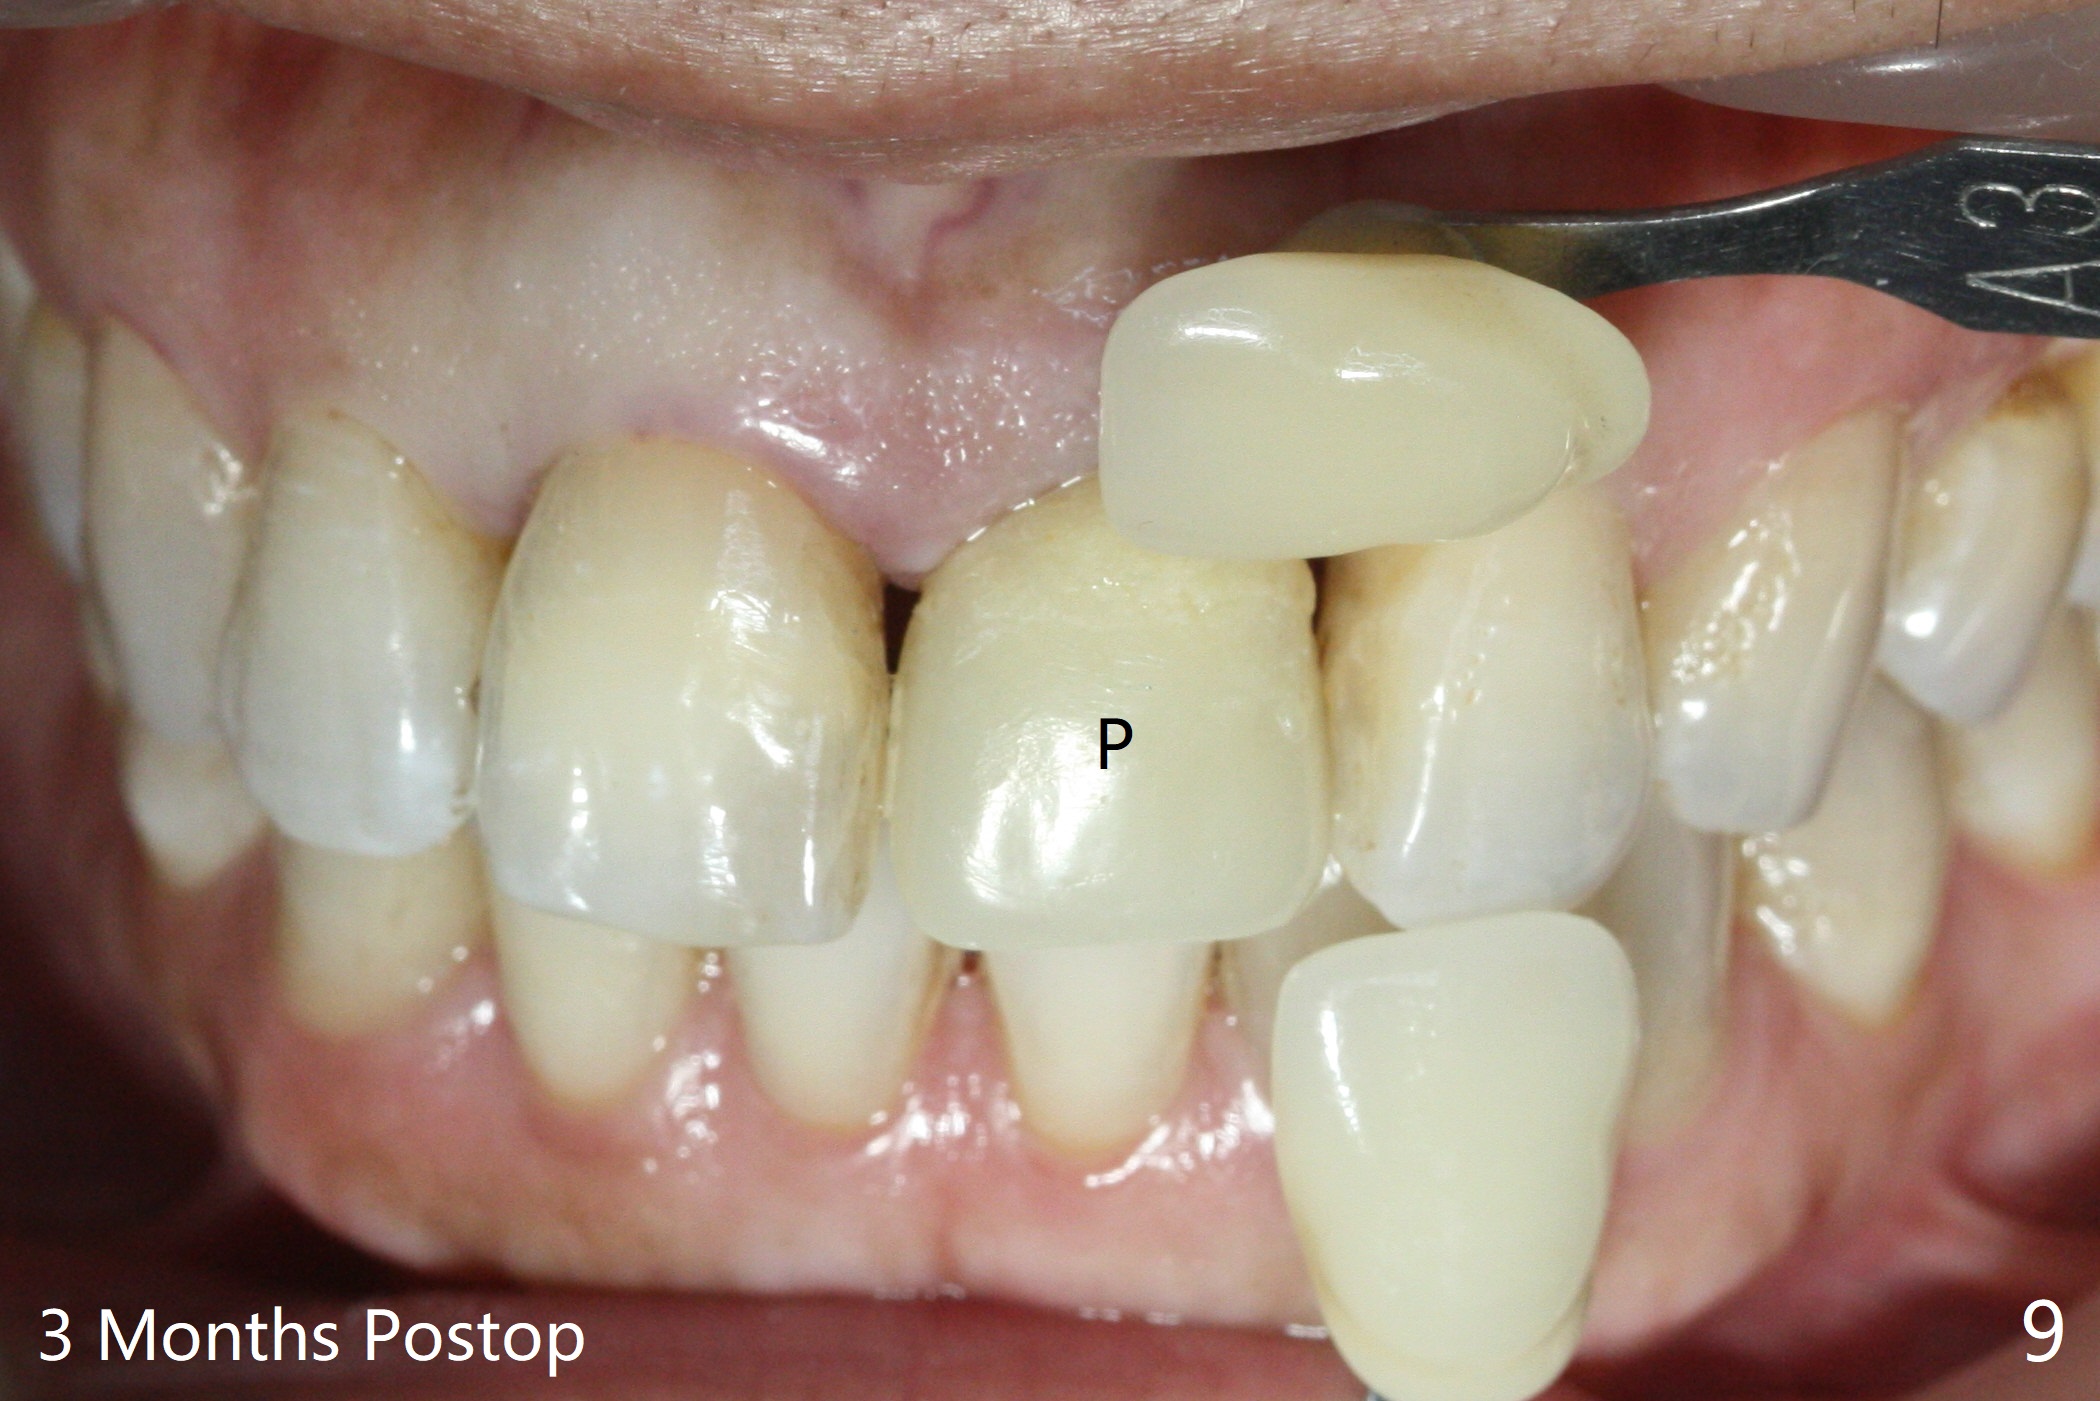

Except the depth, a 2.5x10 mm mini implant is placed with precision (in trajectory) at #9 (Fig.1-5). Confidence using surgical guide for the narrow ridge is enhanced due to placement of two digits against the buccal and palatal plates for tactile sensation. The depth issue is related to overprep with 2.2 mm drills. The torque is <15 Ncm. The immediate provisional is bonded to the neighboring teeth for retention. It appears that smaller drills should be made for guided surgery (such as 1.5 and 2.0 mm). The immediate provisional looks acceptable buccal and occlusal 3 weeks postop (Fig.6,7), although the palatal gingiva is erythematous (Fig.8, which is common after use of drill for access (tissue laceration), OHI offered). Three months postop (Fig.9), the palatal gingiva looks healthy (data not shown), while there is no bone loss around the implant (Fig.10). It remains the same 5 months postop (immediately post cementation, Fig.11) and 3,11 months post cementation (Fig.12,13). The labial gingiva is healthy (Fig.14), while the palatal one is less erythematous and edematous (Fig.15) than earlier (Fig.8).